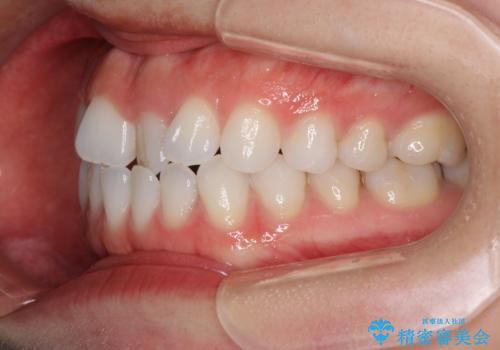

- 上下の前歯の反対咬合を気にして来院された患者様です。

インビザラインを用い、下顎はIPR(歯と歯の間を削る)と歯列全体を後方に移動させ、上顎は前歯を持ち上げることで、反対咬合を改善していくこととしました。

インビザラインによる反対咬合の改善は、上の歯が下の歯を乗り越えていく期間に咬み合わせが非常に不安定となり、治療が長期化することがあります。

こちらの患者様も、一時的に前歯でしか咬めない時期がありましたが、比較的早く咬み合わせが安定し、1年ほどで治療を終えることができました。